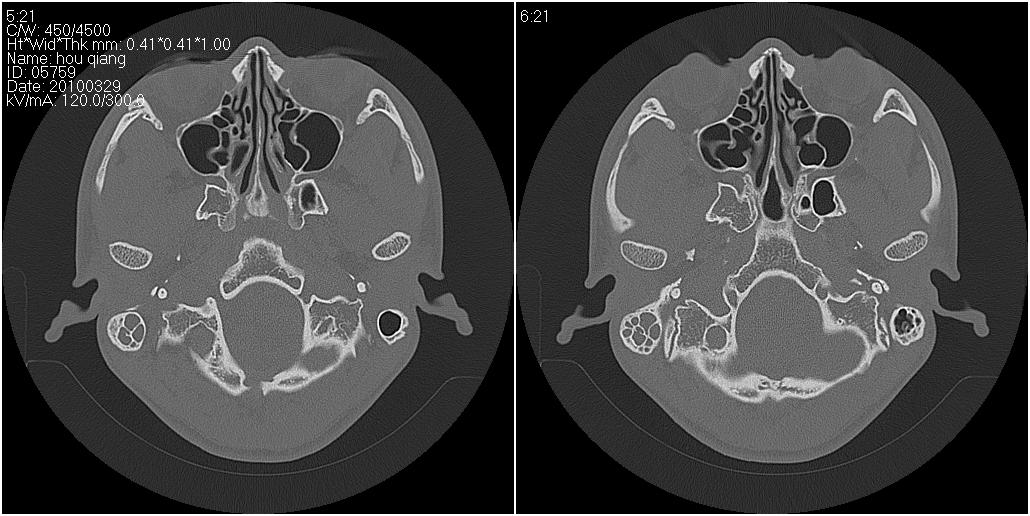

标题: CT25419:男性,18岁。右耳肿、痛5个多月。 [打印本页]

标题: CT25419:男性,18岁。右耳肿、痛5个多月。

右侧中耳乳突炎累及外耳道,鼻咽腺样体肥大。

1)右侧慢性中耳乳突炎并右侧中耳腔及外耳道肉芽肿或胆脂瘤形成。2)鼻咽腺样体肥大。